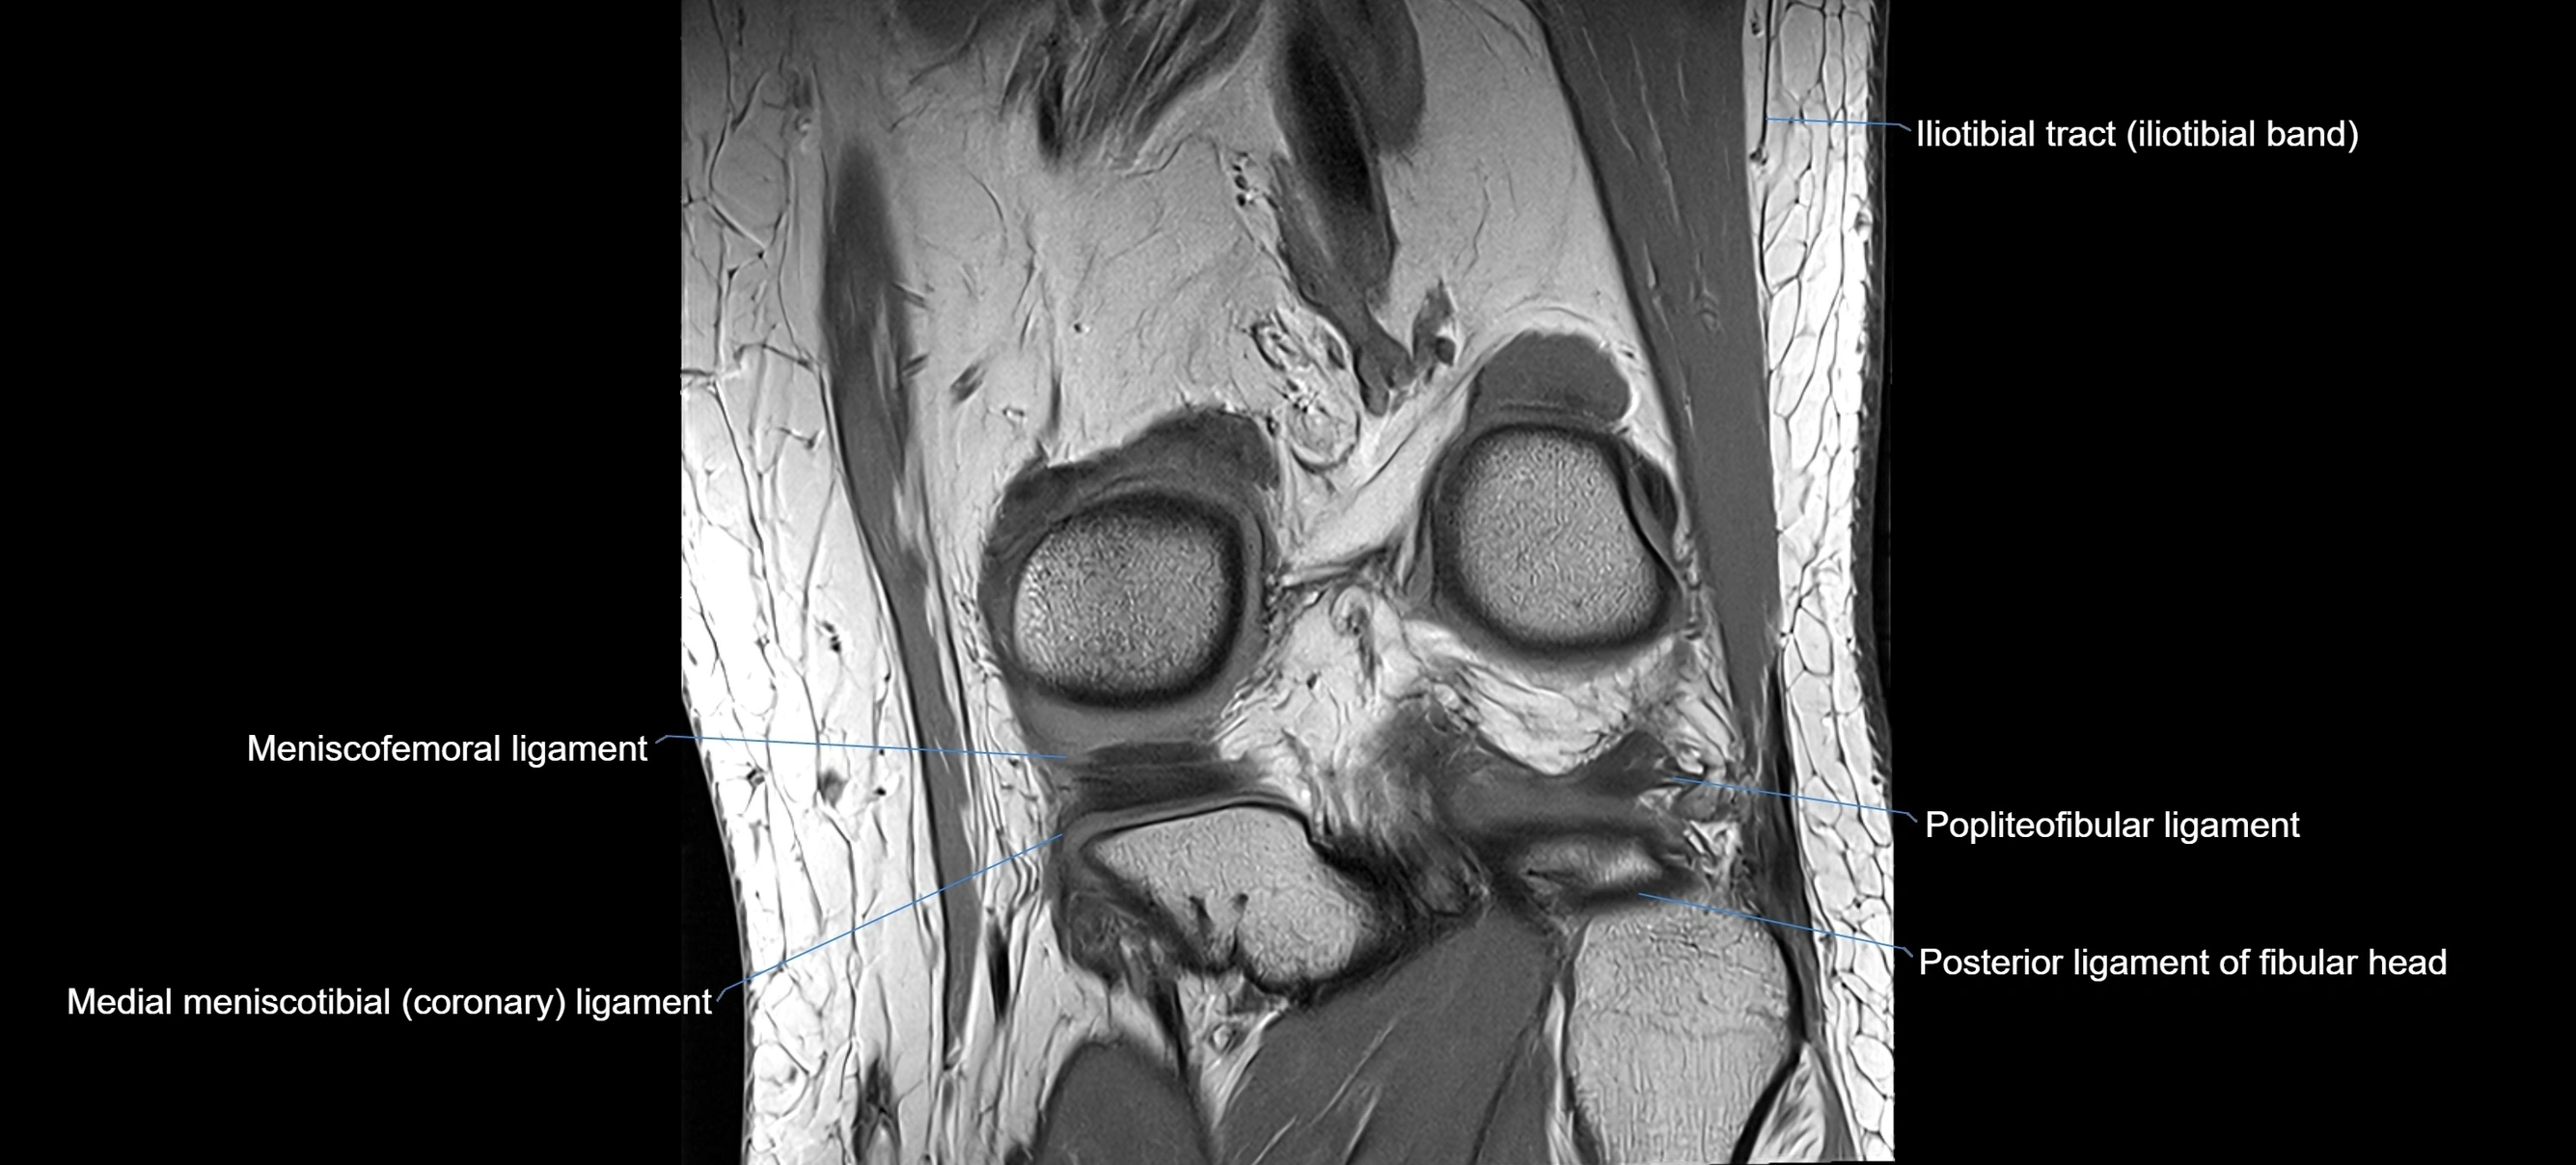

MRI images

image